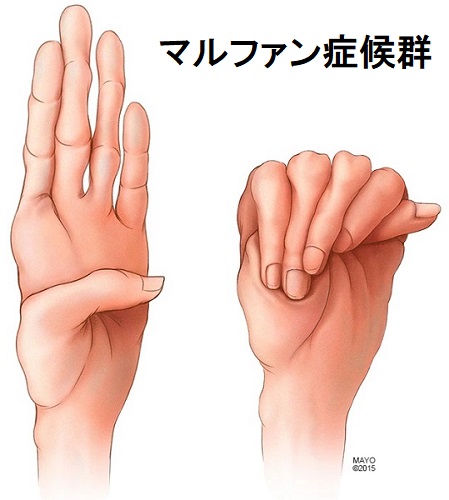

マルファン症候群(marfan syndrome:MFS)は、常染色体優性遺伝性の結合組織異常。フィブリリン-1(fibrillin-1)をコードするFBN1遺伝子やTGF-β 受容体遺伝子の突然変異により、過剰TGF-βの臓器沈着からコラーゲン形成障害が生じます。

マルファン症候群の身体的特徴として、高身長で四肢の指が長い、胸郭の変形、眼の水晶体亜脱臼などがあります。